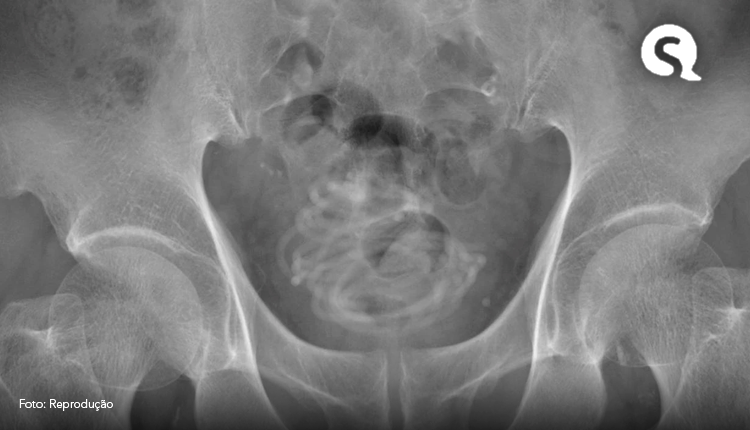

“Primeiro realizamos um ultrassom e identificamos um objeto grande na bexiga do paciente. Depois fizemos um raio-x, que revelou um corpo estranho enrolado em forma de fio. Em seguida, fizemos uma tomografia que nos ajudou a escolher o melhor jeito de tirar a corda e usamos um programa de computador em 3D para nos direcionar. Percebemos que seria impossível puxar a corda pelo pênis”, disse Toshiki Kijima, professor de urologia na Dokkyo Medical University, autor do documento.

Legenda: Imagens obtidas pela equipe médica

Foto: Reprodução/Urology Case Reports